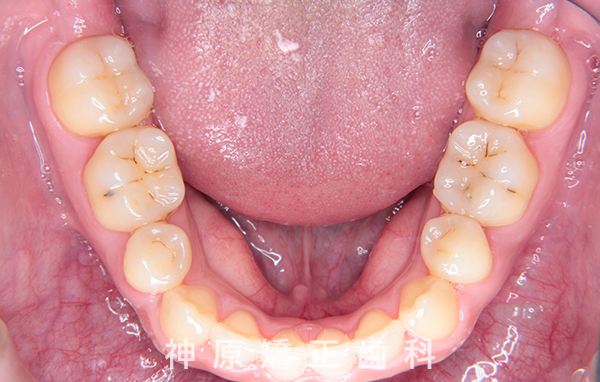

19歳 男性

症例02

- 下の歯が前に出ている

- 19歳8ヶ月、男性

- 2年4ヶ月

初診時

精密検査の結果、大きな骨格的なずれはありませんでした。しかし、あごと歯の大きさのバランスが悪く、すべての歯を並べると横顔の見た目が悪化する可能性がありました。また、適切な歯軸の獲得も難しい状況でした。そのため、小臼歯を抜歯して適切なスペースを確保し、歯並びを整えることにしました。これにより、ガタガタした歯並びや前歯の噛み合わせの問題が改善されました。